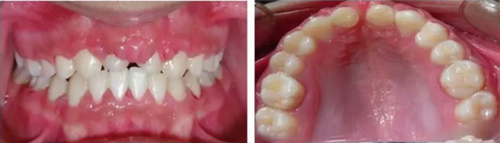

車禍后,一名10歲男孩被送往Shariati醫(yī)院急診科。診斷出上頜中切牙的脫落和側(cè)切牙的嵌入(圖1)。脫落的中切牙丟失了,沒(méi)有進(jìn)行再植。全景片示除第二磨牙外的恒牙列(圖2)。

圖2. 初診全景片